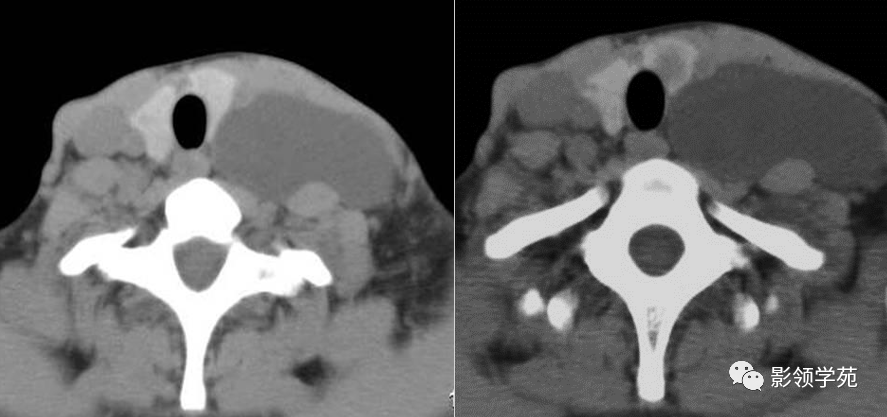

皮样囊肿:临床特征:舌骨中线缓慢生长肿块,质软,与皮肤不粘连.